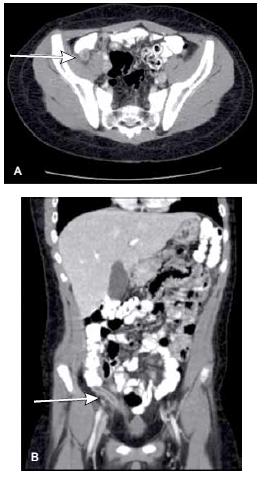

Homem de 19 anos deu entrada na emergência com sintomas e sinais de abdome agudo. A tomografia computadorizada do abdome está demonstrada a seguir.

Com relação a este caso, pode-se afirmar que,